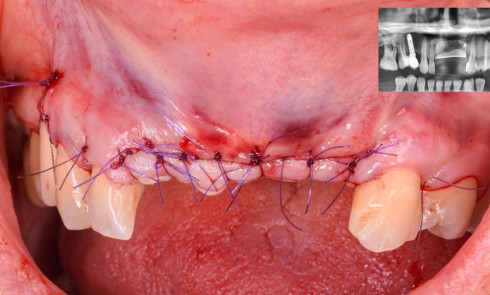

Quelles sont les spécificités de la pressée sur zircone ? Quelle est sa mise en oeuvre ? Comment analyser les échecs pour une fiabilité à longue échéance ?

Le traitement implanto-prothétique des édentements complets mandibulaires en présence de résorptions sévères représente un défi chirurgical et prothétique majeur. Cet article...